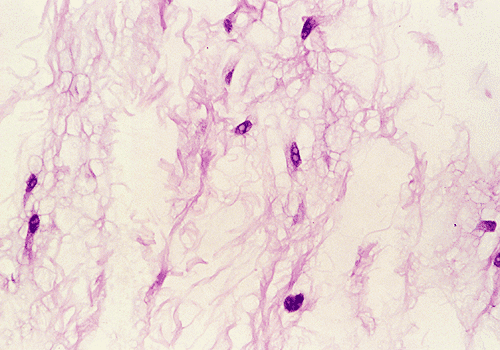

The biopsy material contained several small cores of tissue. Panel B is a low-magnification photo that showed a myxomatous lesion on one side with some linear mature bone trabeculae on the other side. This area probably represented the thinned out residual cortical bone. Panels C and D are higher magnification photos of the bone trabeculae in Panel B. No osteoclastic activity is evident. Panel E shows small, mature bone spicules that are surrounded by myxomatous tissue. The hypocellular and myxomatous nature of the lesion is well demonstrated in Panel F. Panel G and H are high magnification photos from different areas and show a modest number of collagen fibers within a myxomatous background. The bland features of the tumor cells are also well illustrated.